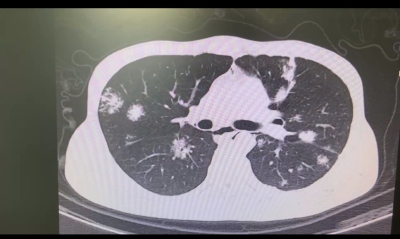

周圍型結節:“肺城郊區”的隱世妖怪

周圍型結節如同住在“肺城”四周的隱世妖怪。

它們長得比較靠邊,離肺門、支氣管和血管都比較遠,仿佛住在城市的郊區,遠離了喧囂。這就像《西游記》里在深山老林修煉的妖怪,看似與世無爭,但其實也暗藏玄機。周圍型結節可能和肺部感染、結核或者一些腫瘤之類的疾病有關,就像那些隱世妖怪也會時不時出來搞點破壞。

它們可能在不知不覺中慢慢威脅著“肺城”的健康,就像山林中的妖怪悄悄積攢力量,準備給取經隊伍來個突然襲擊。